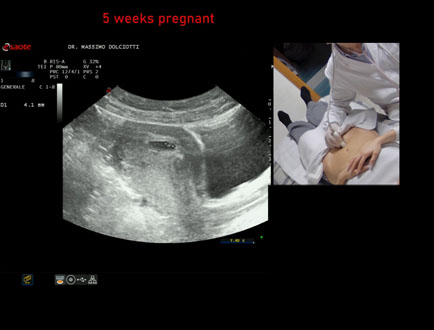

Data inserimento: 06/02/2026

Ecografia del: 28/01/2025

Strumento: Esaote MyLab Eight

Sonda: Convex Multifrequenza 1-8 MHz

Età Paziente: F 28 anni

Motivazione dell'esame: amenorrea.

Commento all'esame: le immagini ed il video documentano la camera gestazionale delle dimensioni di 11 mm e presenza di embrione delle dimensioni di 4,1 - 5,4 mm, con iniziale battito cardiaco.

Conclusioni: gravidanza alla quinta settimana di gestazione (pregnancy in the 5th week of gestation).

In collaborazione: Dr.ssa Marica Manfredi - Ancona, Dr. Ilir Qose - Ancona

Presentazione: Dr. Massimo Dolciotti - Ancona

Elaborazione digitale: Andrea Dini - Ancona